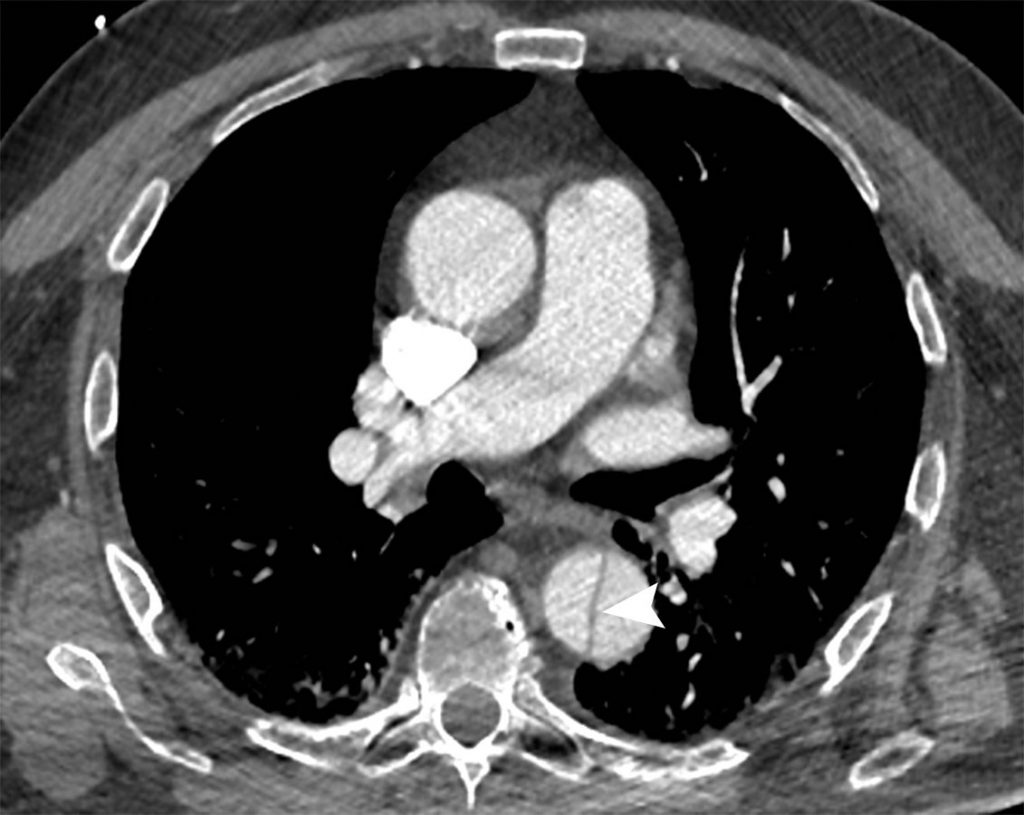

En cas de rupture aortique, l’angioscanner montrera un épanchement péri-aortique (médiastinal et/ou pleural) associé à l’anévrisme (figure 36.6).

Fig. 36.6. Exemple de rupture d’anévrisme de l’aorte thoracique en angioscanner.

Celle-ci se traduit par la présence d’un hémomédiastin autour de l’aorte, d’un volumineux hémothorax gauche. La zone de fissuration est bien visible (flèche). À noter la présence concomitante d’une embolie pulmonaire dans l’artère pulmonaire gauche (double flèche).